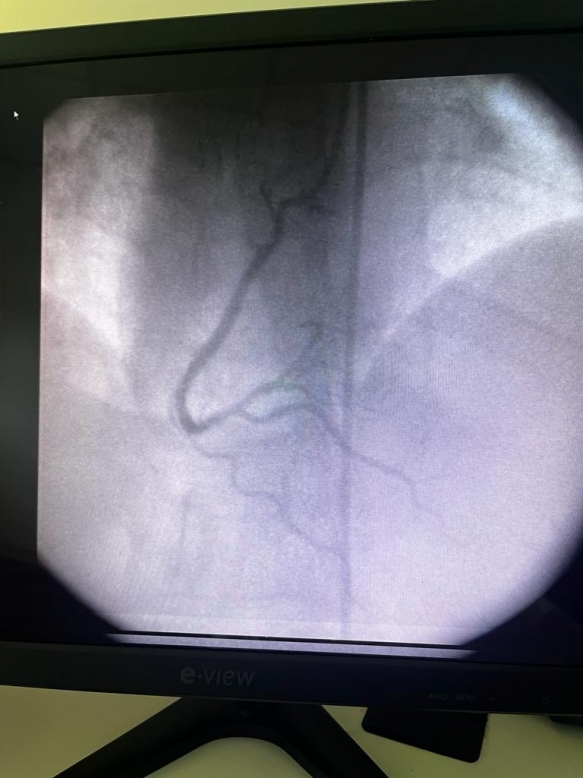

HITO HISTÓRICO EN GESELL: REALIZAMOS EL PRIMER CATETERISMO EN EL HOSPITAL MUNICIPAL "ARTURO ILLIA"

En un hecho trascendental para la salud geselina, el Hospital Municipal "Arturo Illia" llevó a cabo el primer cateterismo gratuito de la ciudad a un paciente de 39 años de edad, que carece de obra social.

El procedimiento de cateterismo cardíaco es una herramienta fundamental para diagnosticar con precisión enfermedades en las arterias del corazón. Permite identificar obstrucciones en las venas o arterias, determinando su grado de afectación y gravedad. La información proporcionada por esta técnica es esencial para comprender la relevancia de las afecciones cardíacas y definir el tratamiento apropiado a cada caso.